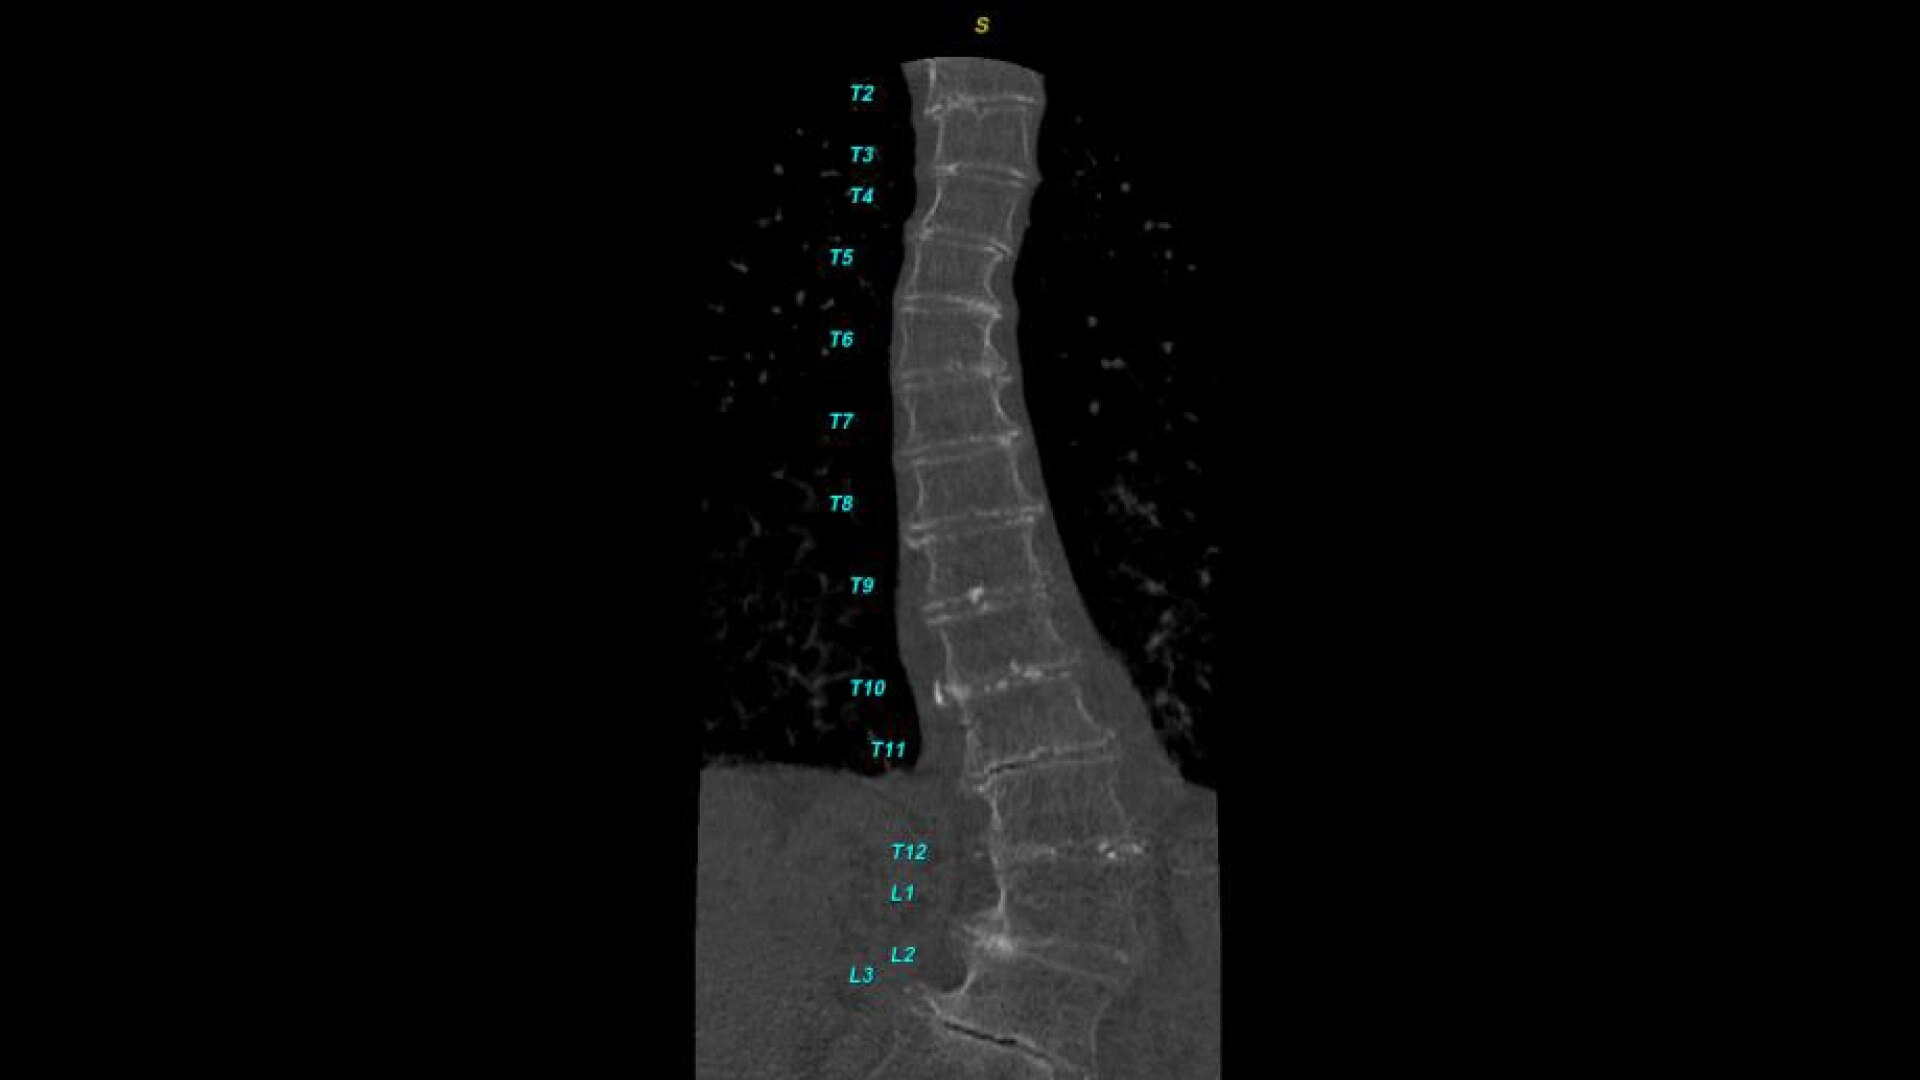

Bone VCAR

Spine assessment with deep-learning based CT application.

• Automated generation of a 3D trace to generate oblique and straightened reformat views

• Automated generation of oblique views perpendicular to vertebral bodies and disc spaces

• Easily edit the centerline to ensure accurate placement in the most challenging cases